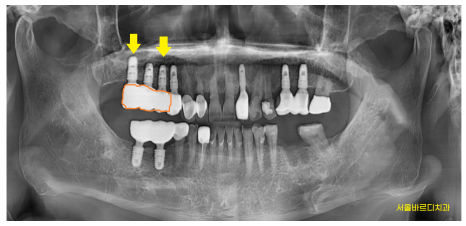

환자분께 설명 드렸던 사진입니다.

동그라미로 표시한 부위가 충치입니다.

단순히 충치만 있는 것이 아니라

한쪽 뿌리 뼈도 많이 녹아

검정색으로 보이네요~

230515

해당 치아는 치료를 하더라도 몇개월 안가

문제가 생길듯 하였습니다

기회비용을 생각하여

당일 문제 치아 발치 후 상악동 거상술을 동반한 뼈이식

진행하였는데요.